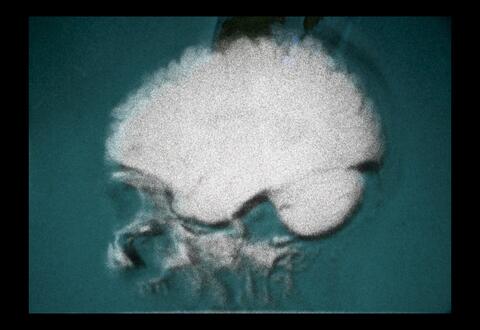

Irina Tempea est une cinéaste et travailleuse culturelle d’origine roumaine basée à Tiohtià:ke/Montréal. Sa pratique artistique de type journal-intime tourne autour du procédé analogique qu’elle utilise afin de se dévoiler. Elle questionne au passage la matérialité de la pellicule tout en filmant son quotidien, ses proches. Dans ma tête, qui traite de sa sclérose en plaques, est son premier film. Irina est titulaire d’un baccalauréat en études cinématographiques de l’Université de Montréal. Elle souhaite aujourd’hui ouvrir le dialogue avec d’autres dispositifs cinématographiques pour les mettre en relation au sein d’une deuxième œuvre intitulée Bica.